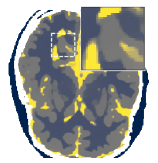

Figure 5 shows an example of a spatio-temporal regularization parameter-map which was estimated using the proposed approach for an acceleration factor of . The network estimates the regularization parameter-map to be pointwise relatively consistenly higher than the spatially required regularization. This result is in fact expected as the temporal dimension is the one for which the gradients of the images are the sparsest because of the high temporal correlation. Further, we see how the network consistently predicts both the spatial regularization as well as the temporal regularization to be less strong in the area where most of the movement is expected, i.e. in the cardiac region.